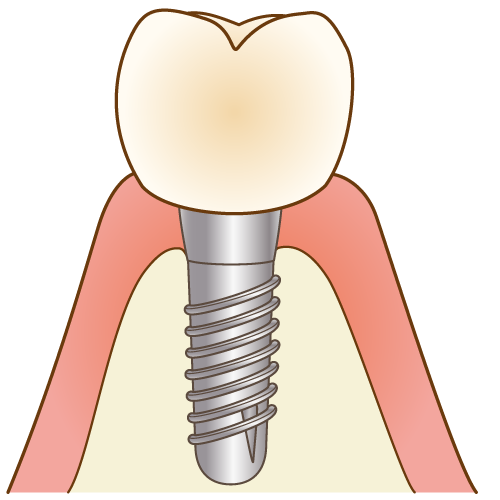

「インプラント」と呼ばれる人工歯根を歯を失ってしまった部分に埋め込み、その上に人工歯を装着することで、まるで自分の歯のような見た目や噛み心地を回復させることができます。

ブリッジや入れ歯と違い、周りの歯や組織に負荷をかけずに歯を作ることができるため非常に健康的で長持ちのする治療です。